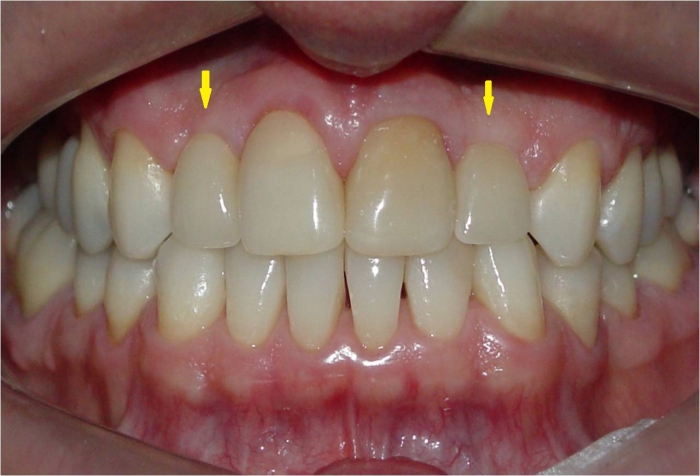

Próteses em porcelana

Sorriso final, do caso terminado em julho de 2012